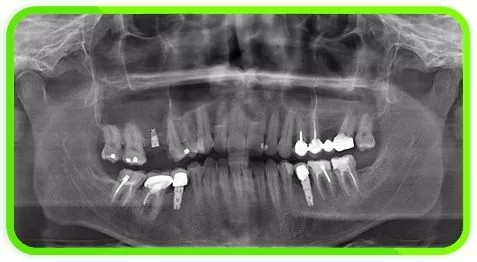

Выбор методики костной пластики определяется только после анализа компьютерной томографии. КТ позволяет оценить объем костной ткани во всех направлениях, а также определить плотность костной ткани.

Благодаря техникам костнопластических операций мы имеем возможность предлагать и устанавливать имплантаты в любую костную ткань независимо от объема. Естественно, при планировании костнопластических операций очень важен индивидуальный подход. При этом учитывается все, начиная от возраста и вида деятельности пациента, заканчивая состоянием его здоровья и необходимости установления имплантатов. Бывают случаи, когда оптимальным решением становится изготовление съемного протеза, несмотря на желание пациента и врачебные навыки и возможности имплантолога. Решение о необходимости костной пластики и установки имплантатов принимается только после тщательного клинико-лабораторно-рентгенологического обследования.